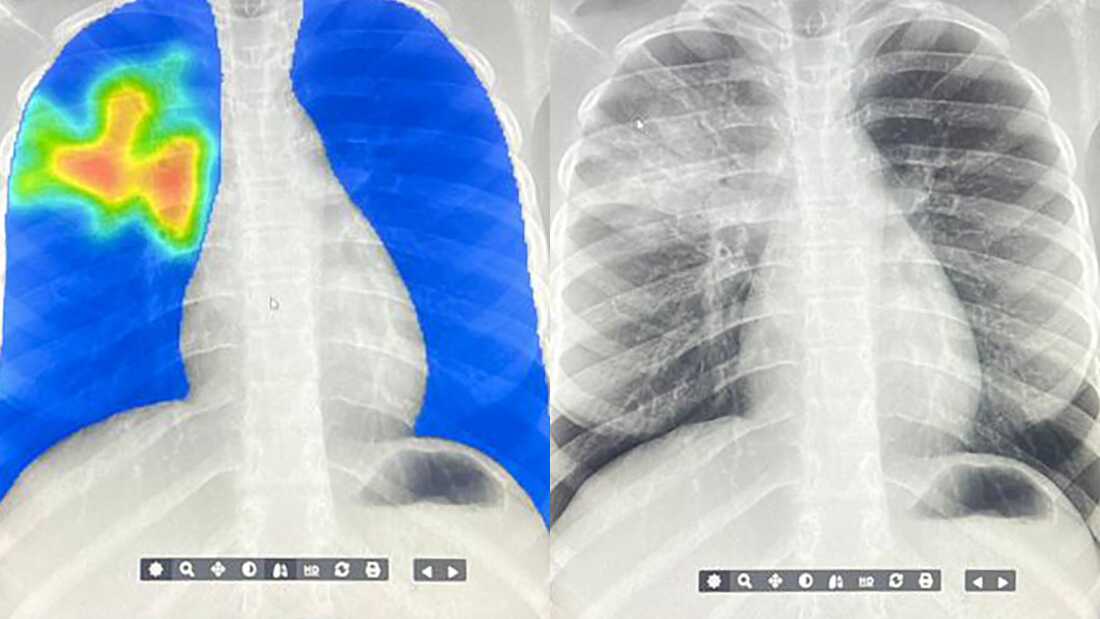

AI is now helping fight tuberculosis, the world’s deadliest infectious disease, in more than 80 low and middle income countries. Health workers use mobile x-ray units that send images to an AI system, which instantly analyzes them and highlights potential signs of TB in bright, heat map style scans. It is catching cases that would have been missed and giving clinics a life saving diagnostic boost.